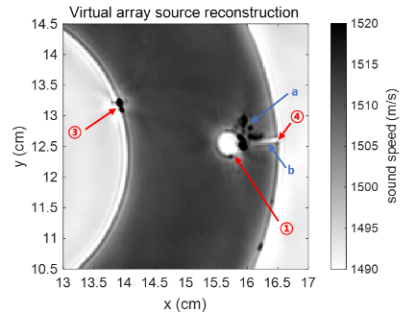

软组织体模的声速参数重建结果如图2所示,体模内外边缘清晰,尺寸和真实尺寸一致。一些已知特征也被成功重建,此外三点钟方向内部孔洞周围的一些破裂和小块脱落也在成像结果中清晰可见。该研究基于实验数据对软组织体模进行定量成像,分辨率可达亚毫米级。

图2 软组织体模声速重建结果(图/赢乐welcome)